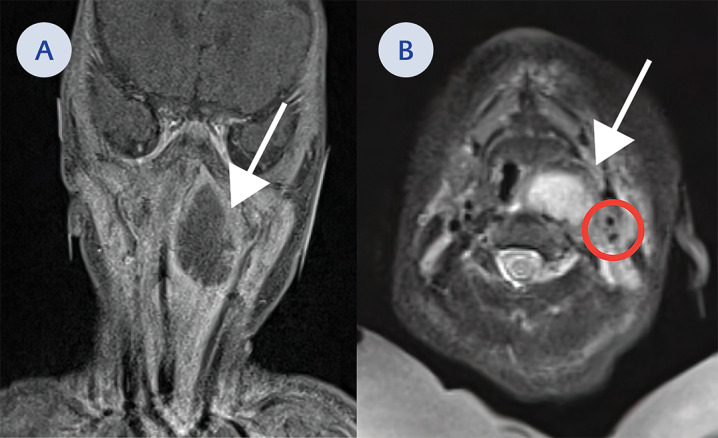

Subsequent magnetic resonance imaging (MRI) of the neck delineated a large 2.6 cm cystic lesion in the left retropharynx consistent with an abscess with ipsilateral lymphadenopathy (Figure 2A, Figure 2B). The patient was taken back to the OR for incision and drainage (I&D). A copious amount of pus was expressed and sent for microbiologic cultures (Figure 3A).

Figure 2.

A. Coronal cut on MRI of a large mass in the left retropharyngeal space (white arrow). This extends from the nasopharyngeal region down to the level of the hypopharynx and just to the margin the larynx. It measures approximately 2.6 cm side to side by 1.8 cm anterior posteriorly and 3.1 cm craniocaudally. B. Axial cut on MRI of large mass in the left retropharyngeal space (white arrow). Red circle indicate location of the left carotid in relation to abscess.